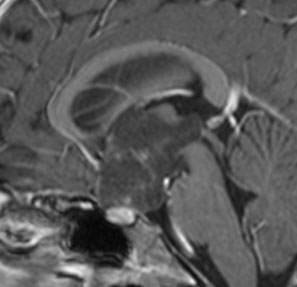

幼児の視路の毛様粘液性星細胞腫です。T2強調画像(左側)で白く高信号に写るのが特徴です。ガドリニウム増強ではまだらになっていますが,均一に真っ白に高信号になることも多いです。乳幼児のものは,ドロドロに柔らかい腫瘍です。

生後7カ月の幼児です。目が揺れるようになり(振り子様眼振)眼科を受診して腫瘍が発見されました。小児脳腫瘍の治療ができる病院へと紹介されました。

1ヶ月後にまたMRI検査がされました。乳児ですから検査にも麻酔が必要です。腫瘍は明らかに大きくなっています。左視神経から視索の腫瘍化が著しいので右側だけかすかに視力が残っているかもしれません。視力は明かりがわかる程度(明暗弁)と評価されました。